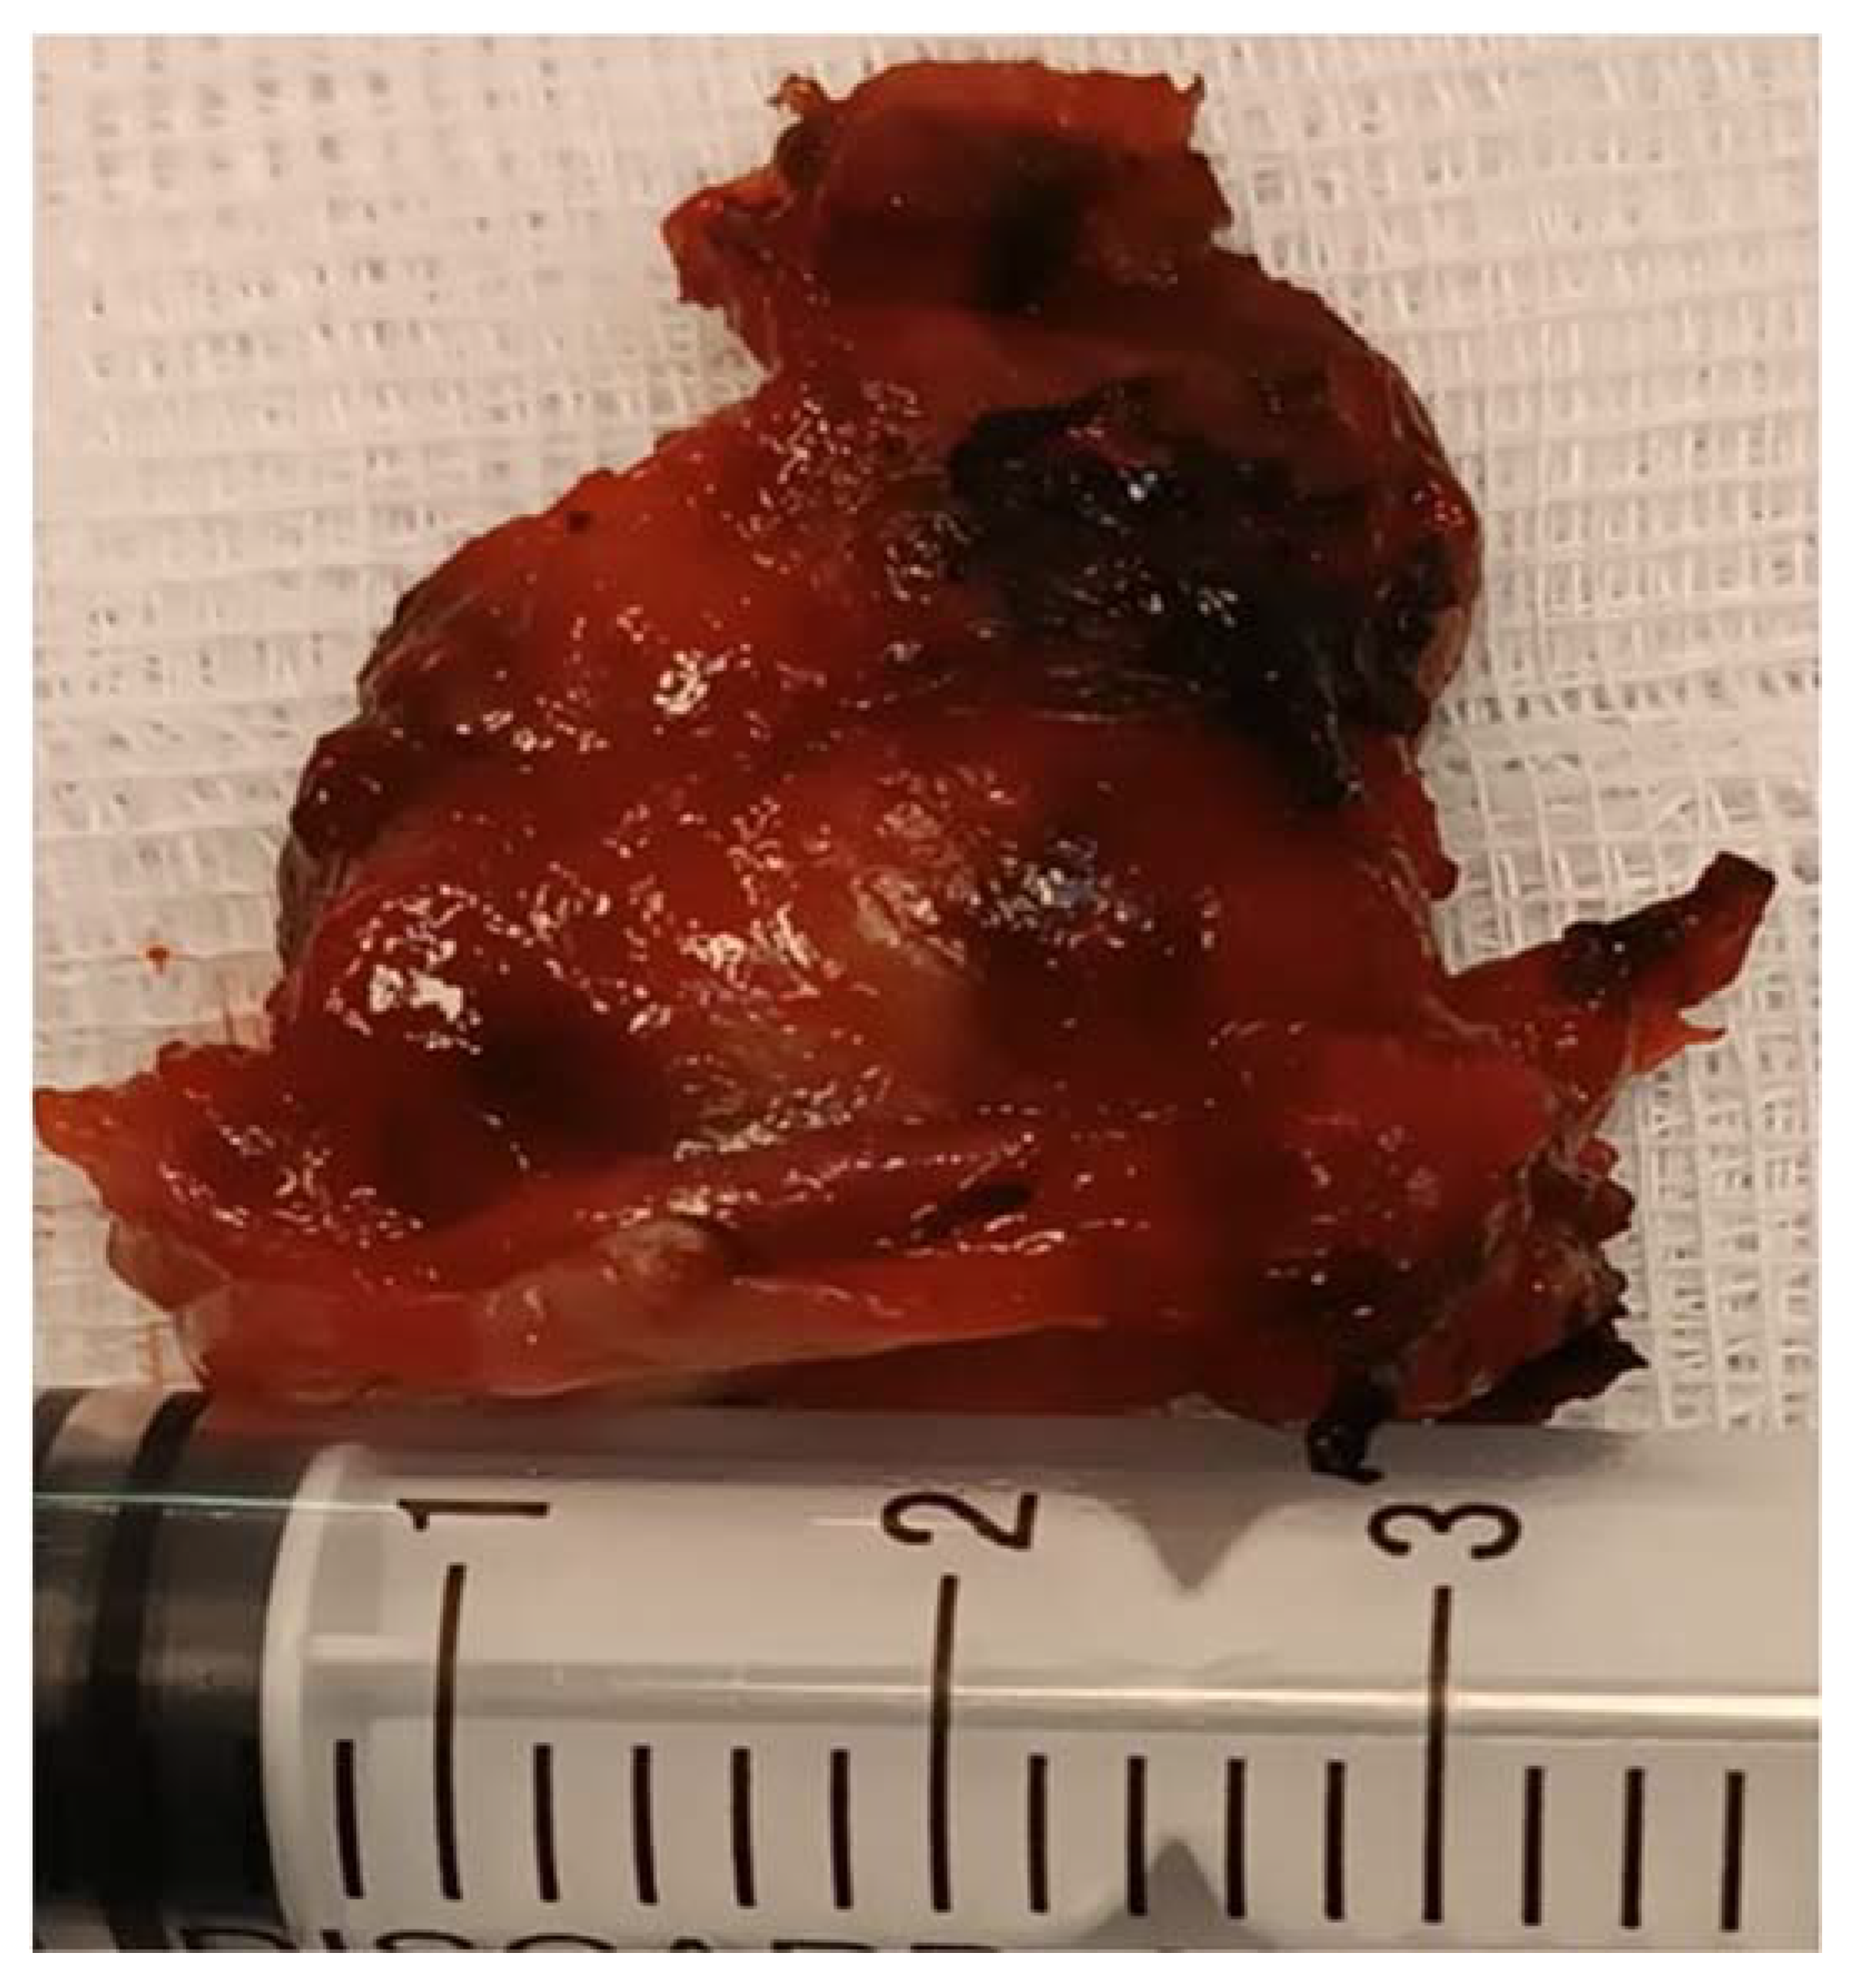

A tumor of 30/30 mm was resected and was sent to the anatomic pathology department (Figure 7). The histological result confirmed the diagnosis of a laryngeal paraganglioma.

Figure 7.

The resected tumor.